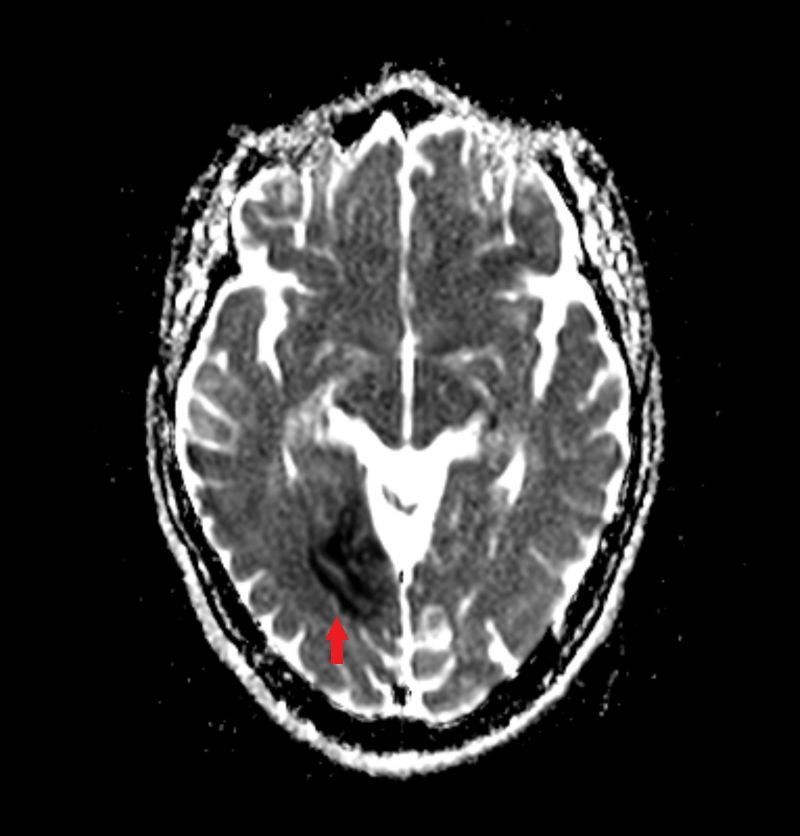

Die diffusionsgewichtete Magnetresonanztomographie (DW-MRT) ist eine spezielle Form der MRT, die die Bewegung von Wassermolekülen im Gewebe sichtbar macht. Dazu wird die Diffusion von Wasserstoffprotonen in verschiedenen Geweben gemessen. Die DW-MRT ist nützlich für die Diagnose von Erkrankungen, die die Diffusion von Wasser im Gewebe beeinträchtigen (Diffusionsrestriktion), wie z.B. akute Schlaganfälle, manche Tumore oder einige Formen von Entzündungen. Die DW-MRT kann auch Informationen über die Struktur und Organisation von Nervenfasern liefern, indem sie die Richtung der Diffusion misst. Dies wird als Diffusionstensorbildgebung (DTI) bezeichnet.

Dieser Vorgang wird für mehrere Richtungen des Diffusionsgradienten wiederholt, um die Diffusion in verschiedenen Raumrichtungen zu erfassen. Die resultierenden Bilder werden als diffusionsgewichtete Bilder bezeichnet und können zur Berechnung von Parametern wie dem Apparent Diffusion Coefficient (ADC) verwendet werden, der als

ADC-Karte dargestellt wird.

diffusionsgewichetes Bild bei Infarkt

gleicher Patient mit ADC-Karte